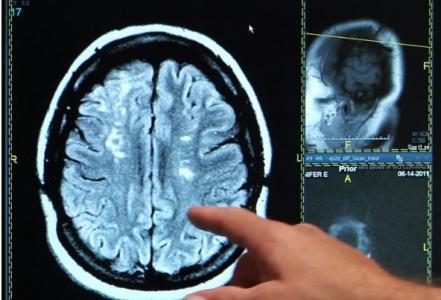

Les chercheurs de l'Université de Surrey (UK), de l'Université de Fribourg (Allemagne) et de l'Université de Berne (Suisse) ont donc mené une étude en laboratoire du sommeil pour comparer les signaux cérébraux de patients post-AVC un an après l’événement vs témoins en bonne santé. Ils ont évalué durant 2 nuits les habitudes de sommeil des patients post-AVC et des témoins par polysomnogramme, un dispositif qui combine des données EEG aux activités respiratoire, cardiaque et aux mouvements oculaires du sujet. L’analyse constate :